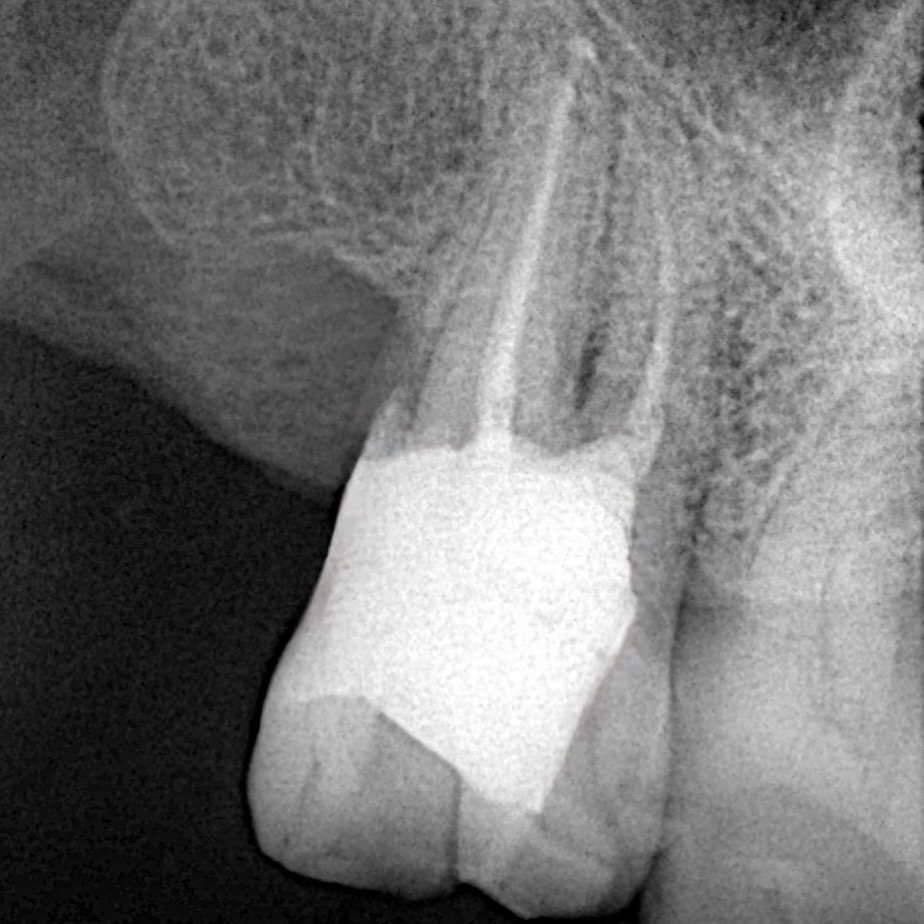

A patient reported with pain and structural compromise of a maxillary posterior tooth. The clinical and radiographic examination confirmed irreversible pulpitis with significant carious destruction extending subgingivally. The treatment plan involved root canal therapy under microscope guidance, followed by biomimetic reinforcement through DME and a cuspal coverage composite onlay.

- Obturation: Warm vertical compaction with bioceramic sealer provided dense, hermetic canal filling.

- Radiographic Assessment: Post-obturation radiograph revealed ideal canal filling.

- Clinical Outcome: The restoration achieved structural reinforcement, margin relocation, and lifelike esthetics. The cuspal coverage composite onlay distributed occlusal forces, reducing risk of catastrophic fracture.